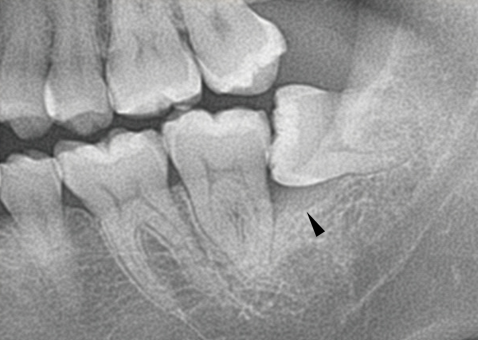

親知らずが横(水平)に生えている写真です。隣の歯との隙間は歯磨きすることは出来ません。放っておくと、次の写真の様になります。

左の親知らずは、大事な一本前の歯を虫歯にし、さらに周りの骨を溶かしています。こうなってからでは遅すぎてしまいます。